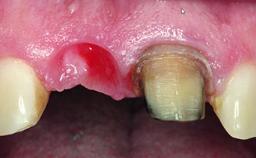

A 30-year-old patient presented at our clinic with a chief complaint of pain in her endodontically treated right maxillary central incisor (tooth 11) with a post-and-core and a fixed single crown. She had a very high lip line, a medium to thin soft-tissue phenotype, and a medium scalloped gingival contour. She also had high esthetic expectations because of her young age and beautiful smile. However, her expectations were realistic and she understood the risks of the treatment. At the initial clinical examination there was a slight mobility of tooth 11; no fistula was observed. The patient also had a single crown on the adjacent tooth 21. Both restorations were old and esthetically deficient. A digital periapical radiograph showed a very small periapical radiolucency, a thick intraradicular post, and no separation between root fragments.

Soft Tissue Grafting Simultaneous